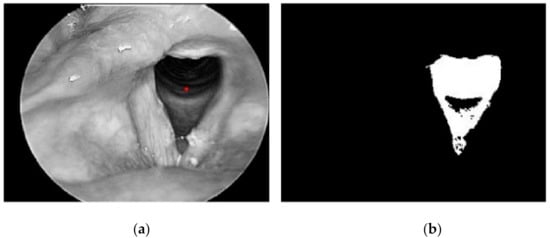

- alternative analogue models have been found in the field of medicine where modelling vocal cords follow a similar pattern;

- Kuo, C.-F.J.; Chu, Y.-H.; Wang, P.-C.; Lai, C.-Y.; Chu, W.-L.; Leu, Y.-S.; Wang, H.-W. Using image processing technology and mathematical algorithm in the automatic selection of vocal cord opening and closing images from the larynx endoscopy video. Comput. Methods Programs Biomed. 2013, 112, 455–465. [Google Scholar] [CrossRef] [PubMed]